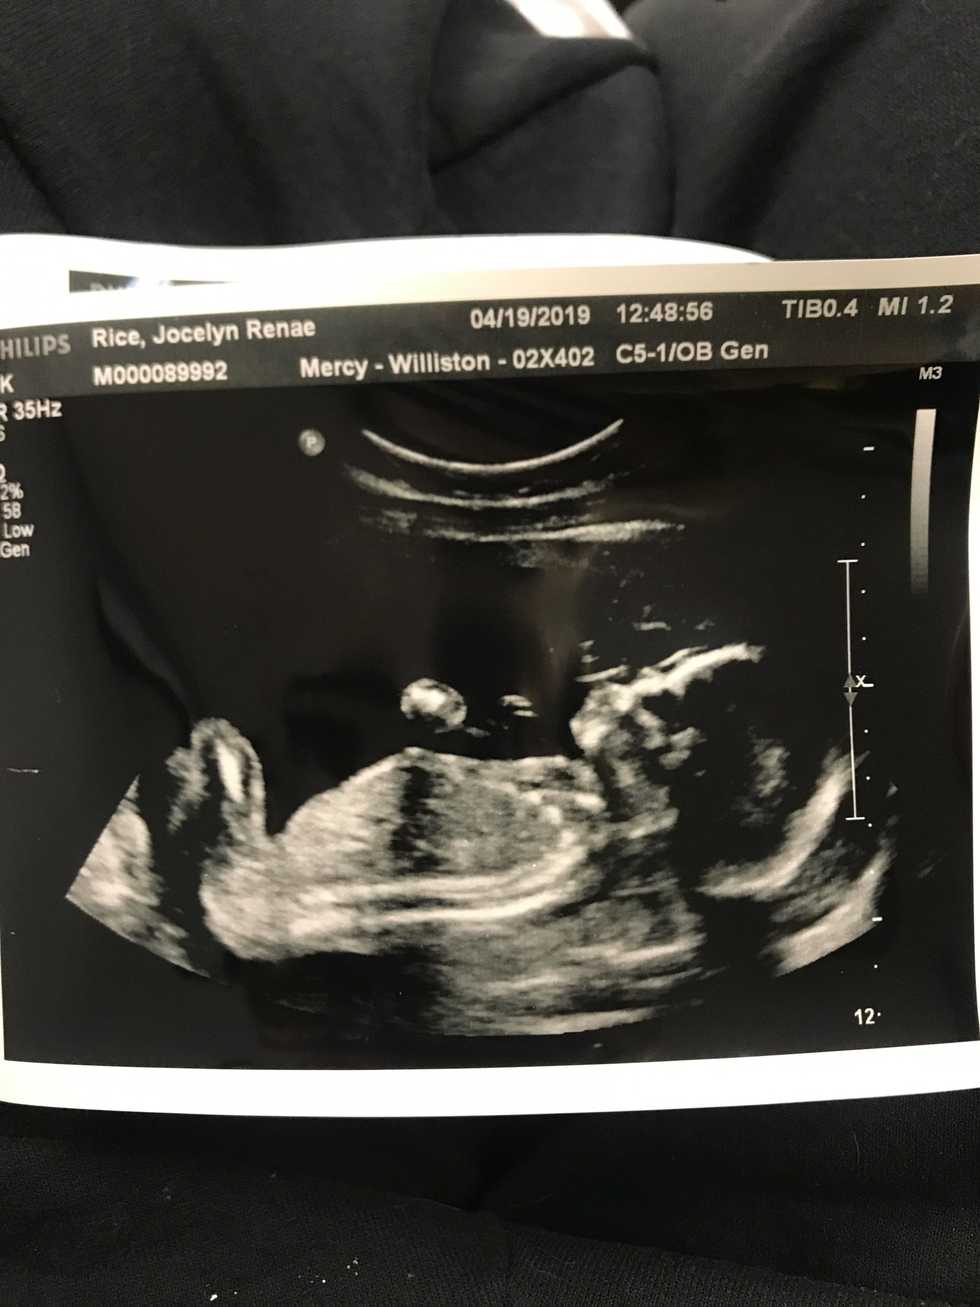

I was 7 weeks pregnant when I first saw the little "bundle of cells" growing inside of me. It's heartbeat was too small to hear, but was detected on the ultrasound. I looked at that ultrasound screen, and for lack of better words, I was PISSED. My husband squeezed my hand with tears in his eyes and said "Look honey! That's our baby!" I couldn't even force myself to smile. You see, I had found out that I was pregnant because of the never-ending morning sickness I had been experiencing since just week 3. I thought for sure that I would be farther along when dated via ultrasound, or that I would at least be having twins and that's why I would be so sick. But no, there was just one tiny little parasite inside of me, and I had a LONG ways to go.

There are many women who are very upset with men making laws for something that they will never have to deal with. I get that, I do. But aren't those who are supporting abortion also in a war against the unborn men and WOMEN as well? (The fetus is one or the other already at only 7 weeks!) Aren't we trying to make decisions for someone who doesn't have a voice, while we yell and scream for not feeling like we don't have ours?

I am only half way through my pregnancy. The little bean inside of me is now identified as a little girl. She has nerves and can feel pain. She also already keeps me up at night with her kicks and rolls. She is now a whole pound, and about a foot long. She has a bedroom in our home, and someone (more than one) to love her as soon as she arrives. I have accepted the responsibility of letting her occupy my body while she waits to join this world. While she maybe lives inside of me and can't live without me, I don't feel entitled to infringe upon her rights to see the sun shine, hear the birds chirp or feel the wind on her little face. She has her own brain, her own heart and her own body that does not belong to me.